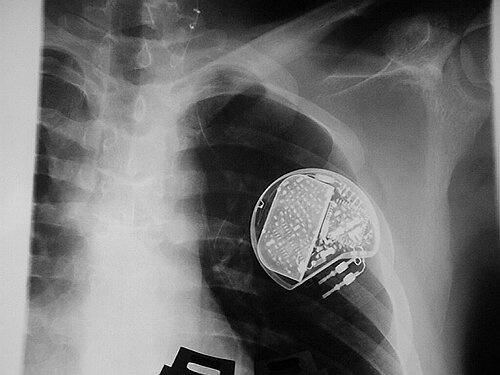

Der Vagusnerv ist einer der 12 Hirnnerven und bildet gemeinsam mit dem Sympathicus das sogenannte "vegetative" Nervensytem, das unter anderem auch Blutdruck und Herzfrequenz steuert. Der Nerv hat am Hals einen Durchmesser von ca. 2-3 mm. Bei der neuen Behandlungsform wird der Vagusnerv in regelmäßigen Abständen über feine Elektroden immer wieder elektrisch gereizt. Dazu implantieren die Bonner Mediziner dem Patienten im Brustbereich einen etwa taschenuhrgroßen Schrittmacher unter die Haut, von dem eine feine Leitung zum Vagusnerv im Halsbereich führt. Die Impulse werden über den Nerv ins Gehirn geleitet und beeinflussen dort die Aktivität von Hirnarealen, die an der Entstehung von Depressionen beteiligt sind. Die Methode gilt als risikoarm und gut verträglich. Gelegentlich während der Stimulationspulse auftretende Nebenwirkungen wie Heiserkeit, Kribbeln in Rachen oder Hals oder eine leichte Veränderung der Stimmhöhe sind nur mild ausgeprägt und insgesamt so geringfügig, dass die Behandlung bisher immer problemlos fortgeführt werden konnte.